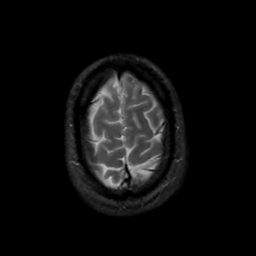

MR Study #14, June 2, 1991 -- Slice #44

[Home][Help][Clinical][Tour 1][Tour 2] Slice 44